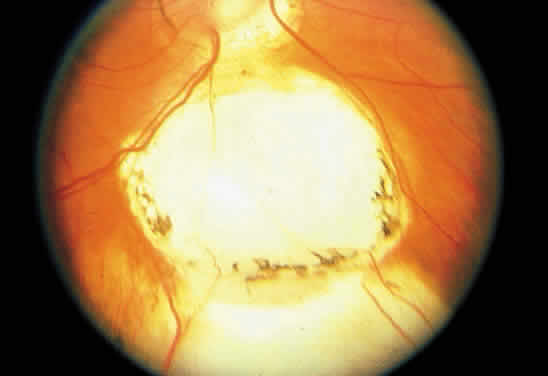

PERIPAPILLARY STAPHYLOMA

A peripapillary staphyloma is a staphylomatous excavation, generally of -8 to -20 D, surrounding the optic nerve.162,163 Although the visual acuity often is decreased with this usually unilateral defect,163,164 normal vision has been reported.165 Most often, the optic nerve head itself appears relatively normal, and atrophic choroidal changes are present surrounding the defect (Fig. 16).

Fig. 16. Peripapillary staphyloma. Notice the relatively normal-appearing optic nerve head within the defect.

Occasionally, the walls of a peripapillary staphyloma can be observed to contract.162,166,167 The reason for this phenomenon is uncertain, although intrascleral smooth muscle has been described in an eye with a congenital coloboma of the optic disc and surrounding staphylomatous defect.168 Pulsations also have been observed in synchrony with respiration.163,169

The anomaly is thought to most likely arise from failure of development of the posterior sclera.162